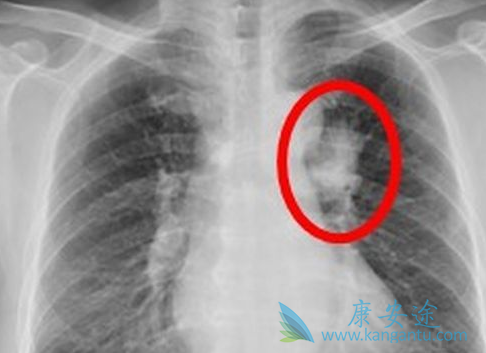

肺癌化疗期间吃什么有助于缓解患者的不良反应

对于发病率和死亡率双高的肺癌来说,化疗也是其治疗的一个非常重要的手段,尤其是对小细胞肺癌来说,化疗是主要的治疗手段。相应的化疗也有很多副作用,临床上经常会有患者家属担心化疗副作用大,家人身体无法承受。那么在临床中是如何评估患者的体质能否耐受化疗呢?大多数情况下,患者需要一般状况较好,血象和肝肾功能正常才能耐受抗肿瘤治疗。下面阐述临床中常见的肺癌化疗不良反应呕吐及处理:

肺癌化疗